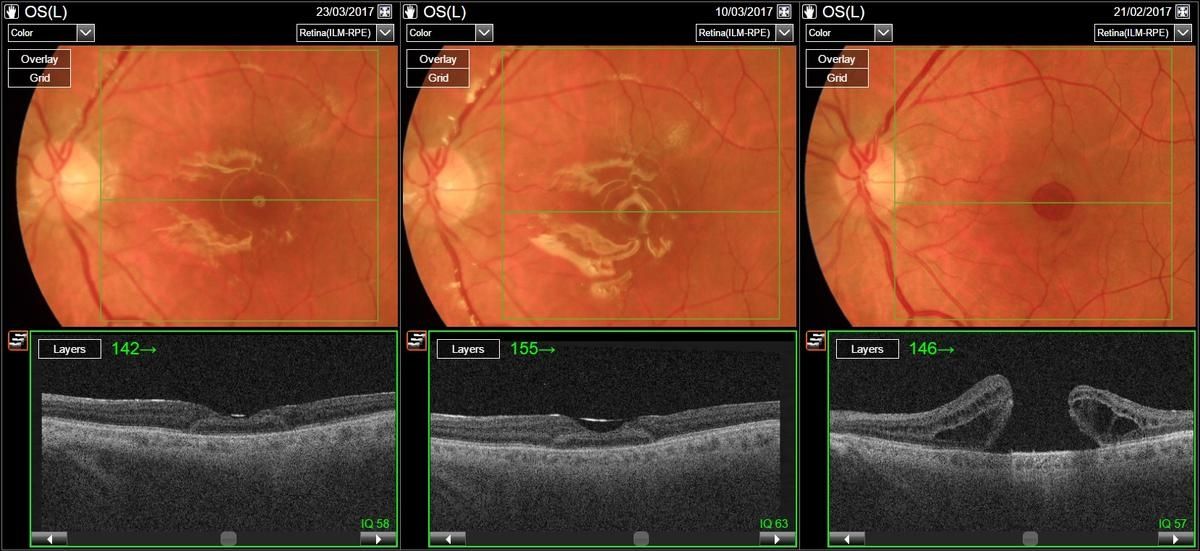

Slike očesnega ozadja (zgoraj) in OCT (spodaj) bolnika po operativnem posegu. Tretja slika v nizu kaže stanje pred operativnim posegom.

Presaditev mrežnice so izvedli pri bolniku z velikim foramnom makule (luknjo v rumeni pegi), ki se s standardnim operativnim pristopom ni zaprl. Makularna luknja nastane zaradi degenerativnih sprememb v steklovini ter nenormalnih vezi med steklovino in mrežnico na področju rumene pege. To lahko vodi do občutnega poslabšanja vidne ostrine, kar bistveno zmanjša kakovost življenja teh bolnikov. Nekateri izmed njih celo povsem izgubijo vid, so sporočili z UKC Ljubljana.

Preberite še

»Med operativnim posegom se del zdrave mrežnice iz periferije presadi na mesto manjkajoče mrežnice v rumeni pegi. V nasprotju z dosedanjimi razmišljanji, namreč da se mrežnica kot živčno tkivo ne da presaditi, te začetne izkušnje kažejo, da se presajena mrežnica čez čas vendar zaraste in integrira v novem okolju ter postopoma prevzema svojo funkcijo. Danes, dober mesec po operaciji, so rezultati zelo obetavni. Prej popolnoma odprta makularna luknja je sedaj s pomočjo presadka mrežnice zaprta. Prišlo je že tudi do rahlega izboljšanja vidne ostrine operiranega bolnika,« je pojasnil Xhevat Lumi.